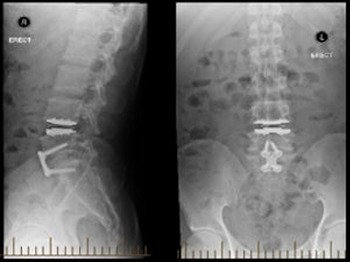

Vary from medical (conservative) treatment along with physio and postural correction to nerve/root blocks (for blocking the affected nerve to give pain relief) to surgical decompression as a last resort (only in 5 pc cases), depending on the severity of the problem